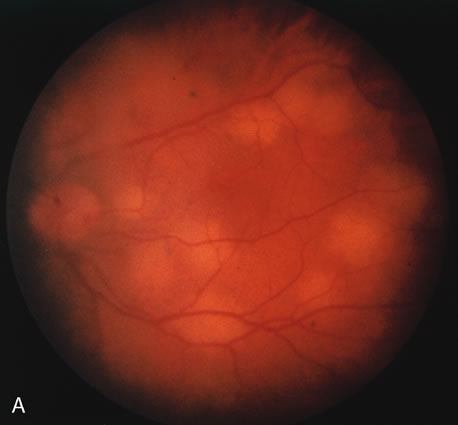

In primary ocular HSV infections, a severe follicular conjunctivitis with regional adenopathy is present. Vesicles may appear on the eyelid skin or lid margin, producing blepharitis (Fig. 3). Corneal involvement initially takes the form of a superficial punctate keratitis, which may progress to dendritic or geographic ulceration. Stromal infiltrates and uveitis are less common and relatively mild in primary disease. In uncomplicated cases, lesions usually heal completely in 2 to 3 weeks without scarring. Most cases of ocular HSV are recurrences. Recrudescent ocular herpes may take the form of dendritic or geographic ulcers, recurrent erosions, interstitial or disciform stromal keratitis, and anterior uveitis.3 HSV may also be an agent of retinitis and acute retinal necrosis (Fig. 4).

The acute retinal necrosis (ARN) syndrome is most often caused by the herpes zoster virus, although occasionally it may be a result of herpes simplex infection.12 It is typically described in healthy patients although association with immunosuppressed patients has also been described. Granular, nonhemorrhagic areas of retinal necrosis may be observed in the fundus, often rapidly coalescing with resulting blindness often caused by retinal detachment. There is often an associated vasculitis and vitritis. In immunocompromised patients VZV or HSV retinitis may also take the pattern of progressive outer retinal necrosis (PORN) (Fig. 6). PORN differs from ARN in that the former is multifocal, localized to the outer retina, and is less often associated with vasculitis and vitritis.